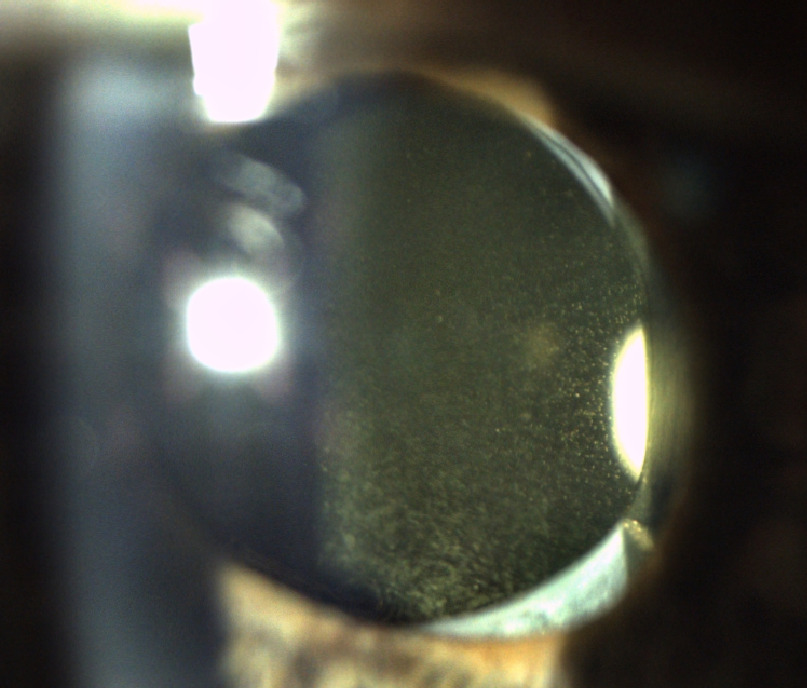

The anterior segment was remarkable for patent laser peripheral iridotomies and PCIOL opacities in both eyes. The opacities reflected light and had a glistening appearance, greater in the left eye than the right eye (Figure 1). Dilated fundus examination was notable for shallow temporal and inferior peripheral retinoschisis of the right eye and a flat choroidal nevus inferonasal in the left eye three-quarters of a disc diameter in size.

In some cases, however, the PCIOL itself can become opacified, a condition known as lens glistening. It is important to distinguish between PCO and glistening as the management of the two conditions differs: symptomatic patients with PCO are treated with YAG laser; patients with lens glistening are managed with observation or require an intraocular lens exchange depending on symptoms and the view of the fundus. A recent review of intraocular lens (IOL) opacifications reported glistening affects vision from induced glare rather than a reduction of acuity or contrast sensitivity.3 The incidence of glistening varies depending on the material of the IOL with 66-100% incidence rates for older hydrophobic acrylic lenses.3 We herein present a patient with symptomatic lens glistening without a reduction in visual acuity.

Glistening IOLs can be differentiated from PCO based on clinical features. In PCO, the IOL opacities are on the inner surface of the posterior capsule. In IOL glistening, the opacities appear within the implant itself. Depending on the severity, PCO or lens glistening opacities can affect a patient’s ADLs or limit examination of the retina.